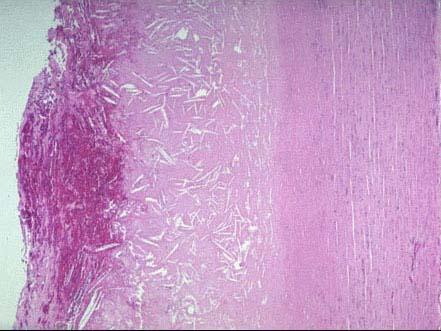

主动脉粥样硬化巨检如图,镜下观如图所示,该病变最佳名称为 ( )A.脂纹B.纤维斑块C.粥样斑块D.粥瘤性溃疡E.动脉瘤形成

问题 主动脉粥样硬化巨检如图,镜下观如图所示,该病变最佳名称为 ( )

选项 A.脂纹 B.纤维斑块 C.粥样斑块 D.粥瘤性溃疡 E.动脉瘤形成

答案 D